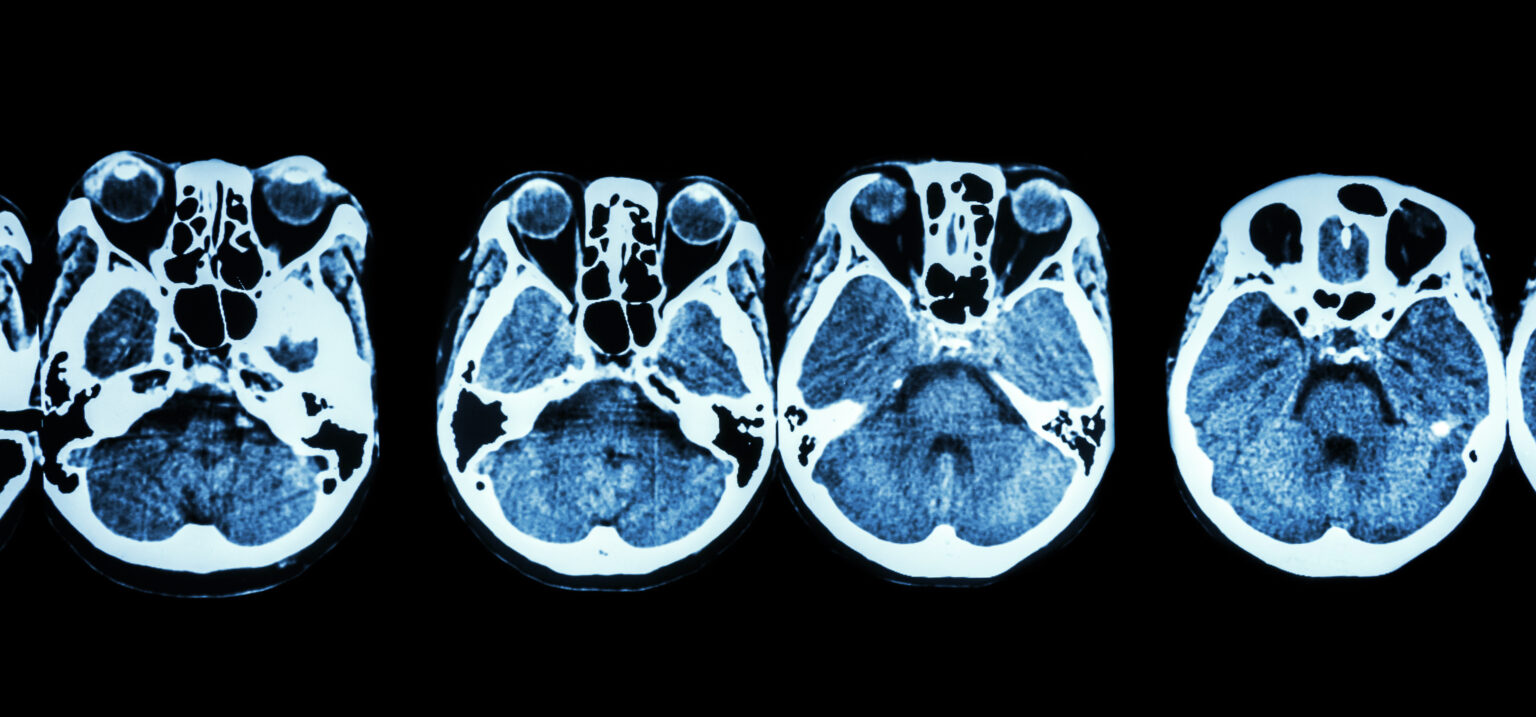

What Would You Get A Ct Scan For . The images are similar to slices of a loaf of bread. Learn why a ct scan is performed and what to expect during one. A ct scan, also called a cat (computed axial tomography) scan, makes layered images of an entire body area. Common reasons for a ct scan of the abdomen are monitoring and diagnosing the following conditions: Ct lung cancer screening can detect small growths called nodules that may be cancerous, although most are not. A ct scan can see nearly all parts of the body and is used to diagnose disease or injury as well as to plan medical, surgical or radiation. Ct scans are often used to find cancer, bone fractures, internal bleeding, blood clots, and injuries to the spine and brain.